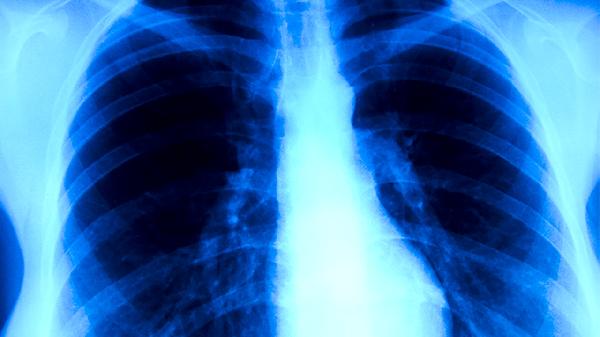

肺结核药物可能引起哮喘发作,但概率较低。抗结核药物中的异烟肼、利福平等可能诱发过敏反应或支气管痉挛,与个体过敏体质及药物代谢差异有关。需结合患者既往哮喘病史、药物使用情况综合评估风险。